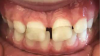

Fig 3. SDF can stain erupting enamel. SDF was applied to the upper incisors while they were still erupting. The enamel at the erupting front (gingival margin) at the time of treatment was immature and porous. Significant amounts of silver penetrated into the enamel and oxidized, becoming apparent. The inciso-gingival extent of the stain shows that only the enamel that had erupted within the previous few weeks took up enough silver to become visible.

Figue 3

Application to erupting teeth in esthetic areas should be considered with caution. It is important to note that permanent teeth crowns can enter the mouth incompletely mineralized. While enamel always goes through a maturation process for years after eruption, in some patients (who do not have amelogenesis imperfecta) the emerging enamel is actually porous and takes at least a few weeks to close.29 This concern is compounded because enamel hypomineralization increases caries risk, and, thus, the children who would benefit most from the preventive effect are also at the highest risk for stain. Figure 3 shows an example of stain at the gingival margin when SDF was applied. The enamel surface gingival to the dark stain shows by contrast that all other exposed enamel may have been more subtly stained. The inciso-gingival thickness of the stain shows that the enamel was no longer susceptible to stain after being bathed in saliva for a few weeks.